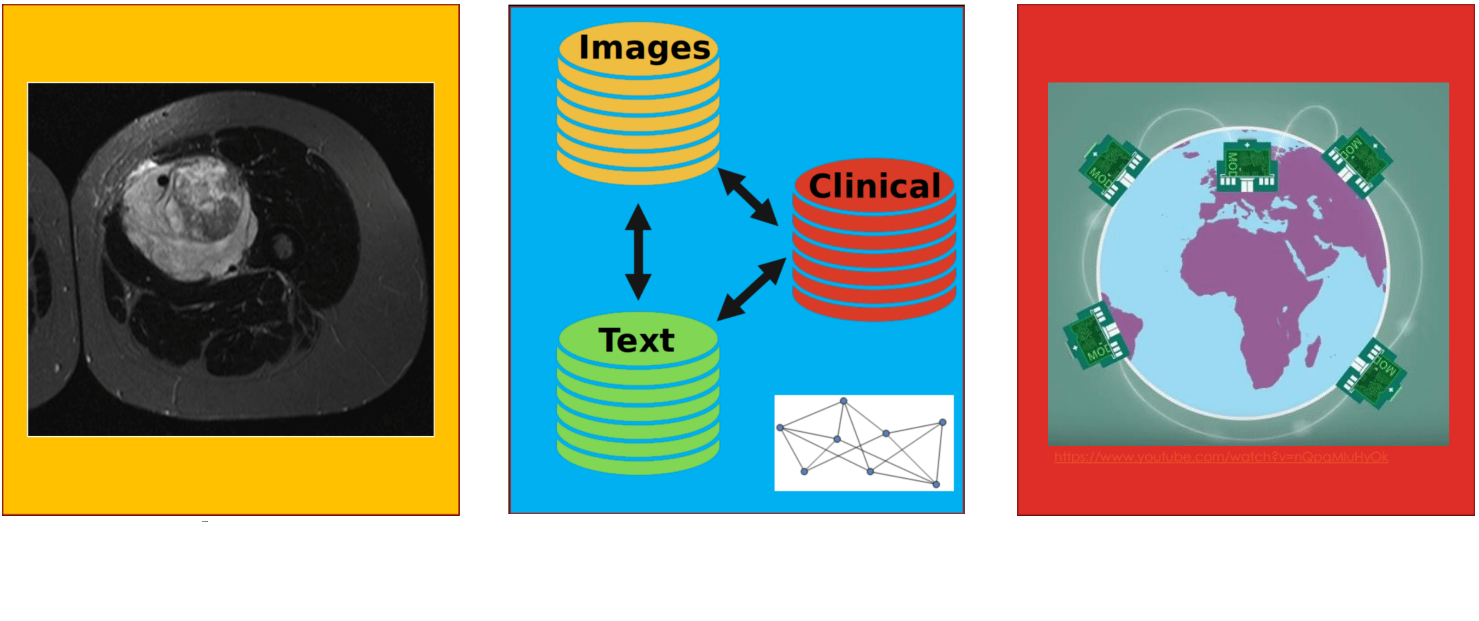

Research Area 1: Medical Imaging

The most aggressive tumors tend to be more heterogeneous

Neural networks can detect the most heterogeneous tumors

Research Area 2: Heterogeneous Data

Data from different sources can be combined to make better predictions

For example, medical imaging, physician text notes and clinical data are full of relevant information

Research Area 3: Federated Learning

To guarantee patient privacy while ensuring maximum use of relevant data

Decentralized learning to ensure medical center sovereignty